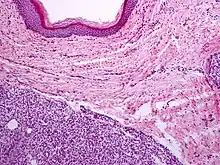

A precise history of the growth characteristics of the IH can be very helpful in making the diagnosis. In the first 4 to 8 weeks of life, IHs grow rapidly with primarily volumetric rather than radial growth. This is usually followed by a period of slower growth that can last 6–9 months, with 80% of the growth completed by 3 months. Finally, IHs involute over a period of years.[34] The exceptions to these growth characteristics include minimally proliferative His, which do not substantially proliferate[33] and large, deep IHs in which noticeable growth starts later and lasts longer.[34] If the diagnosis is not clear based on physical examination and growth history (most often in deep hemangiomas with little cutaneous involvement), then either imaging or histopathology can help confirm the diagnosis.[31][35] On Doppler ultrasound, an IH in the proliferative phase appears as a high-flow, soft-tissue mass usually without direct arteriovenous shunting. On MRI, IHs show a well-circumscribed lesion with intermediate and increased signal intensity on T1- and T2-weighted sequences, respectively, and strong enhancement after gadolinium injections, with fast-flow vessels.[31] Tissue for diagnosis can be obtained via fine-needle aspiration, skin biopsy, or excisional biopsy.[36] Under the microscope, IHs are unencapsulated aggregates of closely packed, thin-walled capillaries, usually with endothelial lining. Blood-filled vessels are separated by scant connective tissue. Their lumina may be thrombosed and organized. Hemosiderin pigment deposition due to vessel rupture may be observed.[37] The GLUT-1 histochemical marker can be helpful in distinguishing IHs from other items on the differential diagnosis, such as vascular malformations.[32]